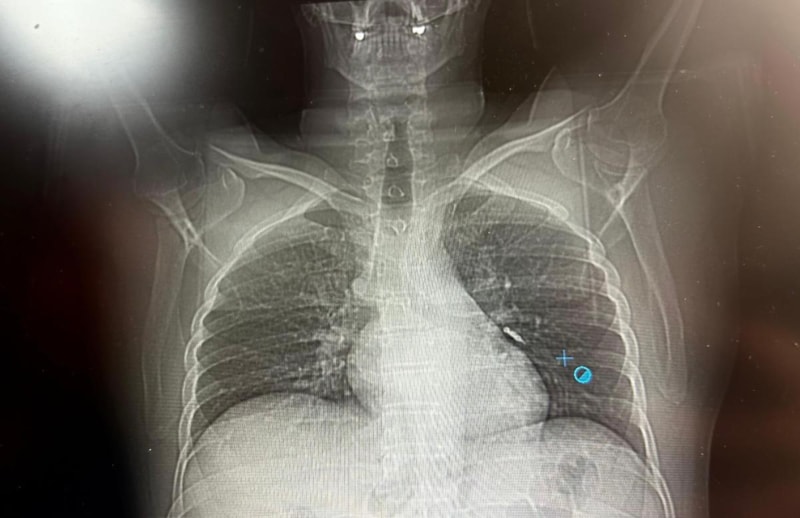

SOL AKCİĞERİN ÜST LOBUNA SAPLANDIĞI TESPİT EDİLDİ

Sol akciğerin üst lobunda saplanmış şekilde tespit edilen vida, vidalı yapısı ve bulunduğu konum nedeniyle güçlükle yerinden oynatılabildi.

İlk olarak hastanenin ek hizmet binasında çekilen tomografi sonucunda, vidanın sol akciğerin hava yollarının yaklaşık dördüncü dalına kadar ilerlediği tespit edildiğini ifade eden Op. Dr. Aksoy, şunları kaydetti:

Daha sonra hasta için yeniden bronkoskopi planladıklarını ancak bu süreçte hasta şiddetli bir öksürük geçirdiğini anlatan Aksoy, "Şiddetli öksürük sonrası yapılan kontrol akciğer filminde implant vidası görünmedi.

Bunun üzerine toraks ve batın BT (bilgisayarlı tomografi) görüntülemesi istedik. Sonuçlarda implantın akciğerden çıktığı ve vücutta herhangi bir yerde bulunmadığı tespit edildi" diye konuştu.